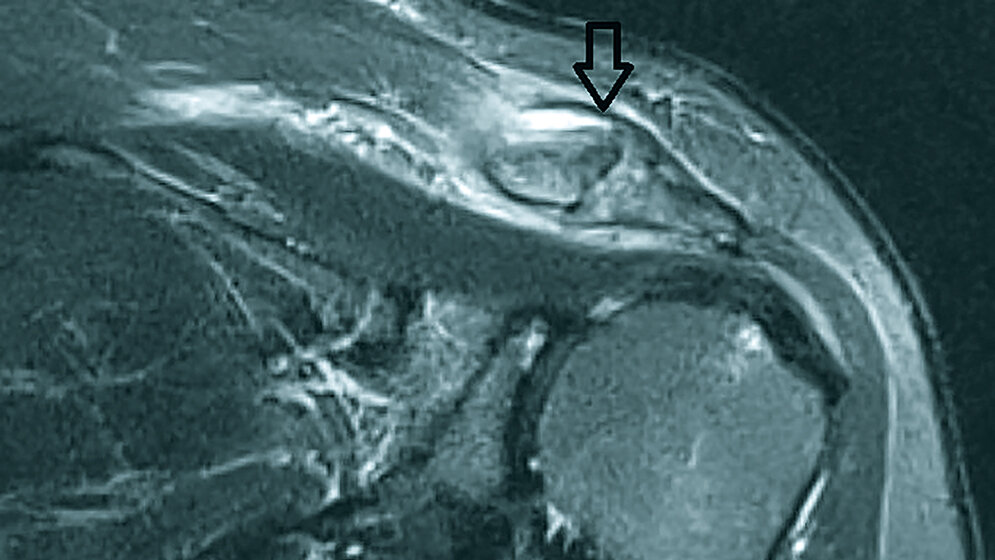

Das Os acromiale ist auf eine fehlende Synostosierung der verschiedenen Knochenkerne des Akromion zurückzuführen. Wenn die konservative Behandlung keine Besserung der Symptomatik bringt, ist die chirurgische Therapie zu überdenken. Die Ätiologie der Entstehung der Anomalie ist noch unklar, und verschiedene Theorien der Entstehung werden diskutiert.

Os acromiale consist in a lack of fusion between the different ossification spots of the acromial side of scapula. When nonsurgical management of a symptomatic os acromiale fails to relieve symptoms, surgical intervention is considered. The etiology of os acromiale is poorly understood, and different hypothesis have been proposed.